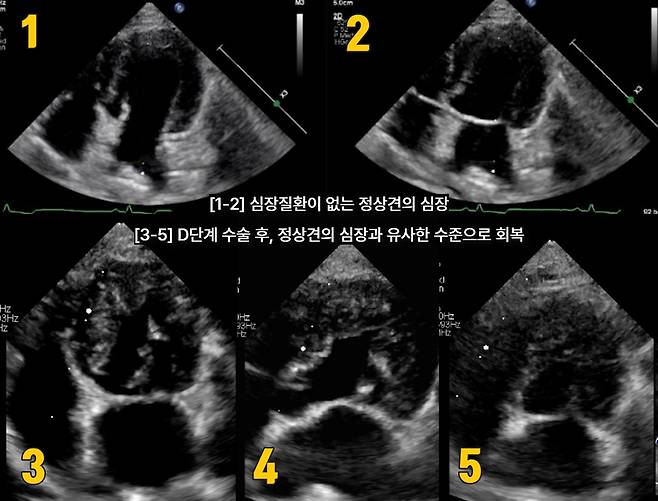

담당 수의사는 판막을 지지하는 조직의 길이를 조정하고 판막과 주변 구조를 교정하는 수술을 시행했다. 수술 후 심장초음파 검사에서 환견의 판막 기능이 정상견과 유사한 수준으로 회복된 것으로 나타났다.